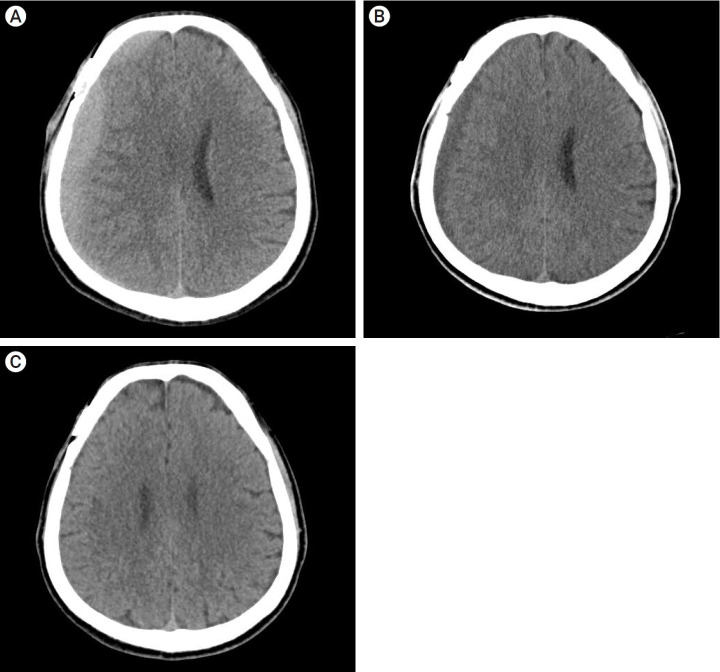

目的:慢性硬膜下血肿(CSDH)是剪切手术后的一种神经并发症。然而,与剪切相关的慢性硬膜下血肿(CSDH)的自然病程和理想治疗方法尚未明确。我们的目的是利用年代学影像学结果研究 CR-CSDH 的病程:我们对 2010 年 12 月至 2018 年 12 月期间在我院接受手术剪切的 736 例未破裂动脉瘤患者中的 28 例(3.8%)发生 CSDH 的患者进行了回顾性分析。患者在夹闭手术后6-8周接受随访CT扫描,并根据患者的症状(基于马克瓦尔德分级量表(MGS)和数字评分量表(NRS))决定是否进行手术干预:在28名患者中,3名患者(10.7%)接受了手术治疗,25名患者(89.2%)的CR-CSDH症状自行缓解。18名患者(64.2%)有轻微头痛,MGS为0-1。平均最大血肿量为 41.9±30.9 毫升(5.8-135 毫升),26 例患者(92.8%)的血肿为均质血肿。血肿消退的平均时间为(126.7±52.9)天(46-228 天)。比较CR-CSDH体积≥43毫升或中线移位≥5毫米的组别,发现保守组和手术组在是否存在线性低密度区(P=0.002)和年龄(P=0.026)方面差异有统计学意义:大多数CR-CSDH病例在4个月内自发缓解。因此,我们建议,尽管CR-CSDH体积相对较大且中线移位,但如果患者症状轻微且有特殊的影像学发现,则应密切观察。

Results: Of the 28 patients, 3 patients (10.7%) underwent surgery, while 25 (89.2%) showed spontaneous resolution of CR-CSDH. Eighteen patients (64.2%) had mild headache with MGS of 0-1. The mean maximum hematoma volume was 41.9±30.9 ml (5.8-135 ml), and 26 patients (92.8%) had homogeneous hematoma. The mean time to hematoma resolution was 126.7±52.9 days (46-228 days). Comparing group of CR-CSDH volume ≥43 ml or a midline shift ≥5 mm, the difference in presence of linear low-density area (p=0.002) and age (p=0.026) between the conservative and operative groups were found to be statistically significant.

Conclusions: Most CR-CSDH cases spontaneously resolved within 4 months. Therefore, we suggest that close observation should be performed if patient's symptoms are mild and special radiologic findings are present, despite its relatively large volume and midline shifting.